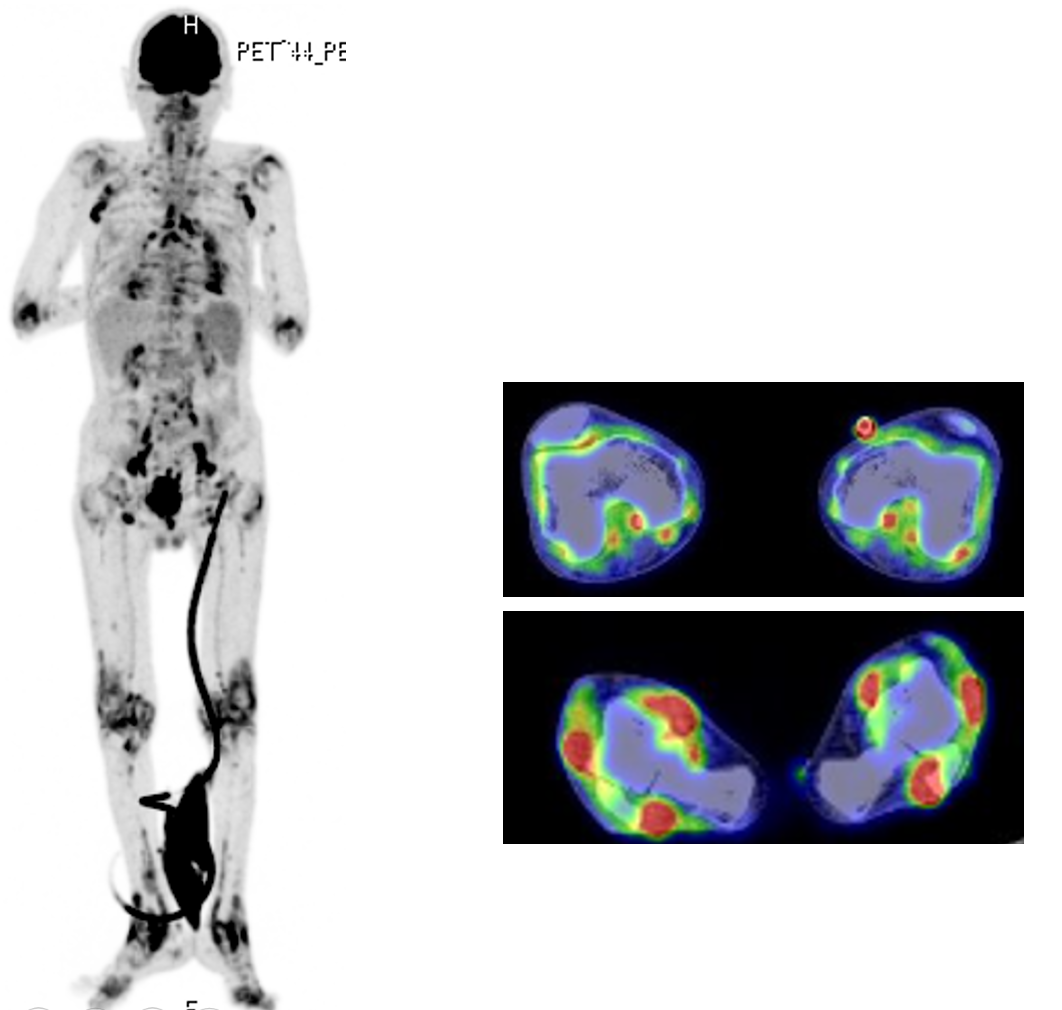

Case Presentation: A 70-year-old man was admitted to our hospital due to prolonged fever and progressive polyarthritis. He had progressive supranuclear palsy and needed a cane when walking. Six-months before admission for his current illness, he had high fever and arthralgia in the right elbow, which was treated with loxoprofen. However, loxoprofen produced only temporary symptom improvement and, as time went on, arthritis developed in other joints as well. His activity levels gradually declined, with progressive debilitation. He was almost completely bedridden at the time of admission. Physical examination revealed swelling and tenderness of the right elbow and tenderness of the left elbow and bilateral shoulder, wrist and ankle joints. Axillary lymph nodes were palpable bilaterally, but hilar lymphadenopathy was not detected on chest radiography. Computed tomography disclosed bilateral pleural effusion and systemic lymphadenopathy including of axillary nodes. He had increased levels of C-reactive protein and soluble interleukin-2 receptor, and absence of rheumatoid factor and anti-citrullinated protein antibodies. Fluorine-18 fluorodeoxyglucose-positron emission tomography detected positive accumulation in axillary, iliac artery, inguinal and mediastinal lymph nodes, as well as bilateral elbow, shoulder, wrist, and ankle joints. Since we suspected a diagnosis of malignant lymphoma, we performed right axillary lymph node biopsy, which demonstrated epithelioid cell granulomas in the specimens. Angiotensin-converting enzyme levels were elevated (35.4 U/mL). We finally diagnosed that his arthritis was associated with sarcoidosis and treated the patient with prednisolone (0.5 mg/kg/day). Thereafter, fever and arthralgia disappeared and his activities of daily life improved from being bedridden to walking with a cane.